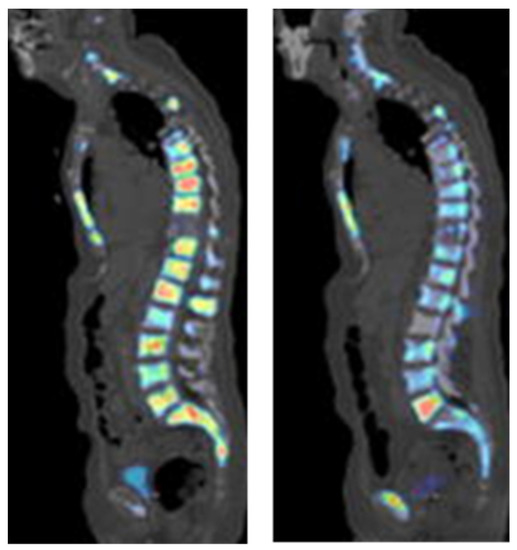

Figure 6. PET images of PSMA expression in PCa (blue arrows) using [68Ga]Ga-PSMA-11 (left image) and [18F]DCFPyL (right image). This research was originally published in the Journal of Nuclear Medicine (JNM) [61].

Figure 7. [18F]Fluoride PET imaging of a PCa patient before (left image) and after (right image) treatment with dasatinib. This research was originally published in the Journal of Nuclear Medicine (JNM) [99].